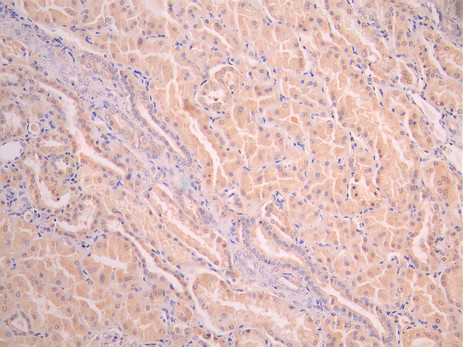

• IHC image of CSB-RA173535A0HU diluted at 1:100 and staining in paraffin-embedded human kidney tissue performed on a Leica BondTM system. After dewaxing and hydration, antigen retrieval was mediated by high pressure in a citrate buffer (pH 6.0). Section was blocked with 10% normal goat serum 30min at RT. Then primary antibody (1% BSA) was incubated at 4°C overnight. The primary is detected by a Goat anti-rabbit polymer IgG labeled by HRP and visualized using 0.05% DAB.

• IHC image of CSB-RA173535A0HU diluted at 1:100 and staining in paraffin-embedded human gastric cancer performed on a Leica BondTM system. After dewaxing and hydration, antigen retrieval was mediated by high pressure in a citrate buffer (pH 6.0). Section was blocked with 10% normal goat serum 30min at RT. Then primary antibody (1% BSA) was incubated at 4°C overnight. The primary is detected by a Goat anti-rabbit polymer IgG labeled by HRP and visualized using 0.05% DAB.